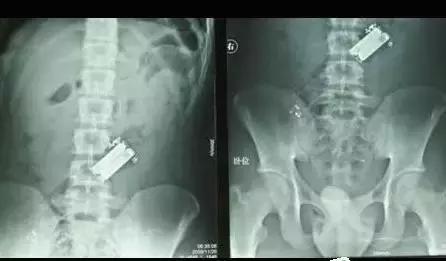

▲电视遥控器

▲犯人私藏的手机